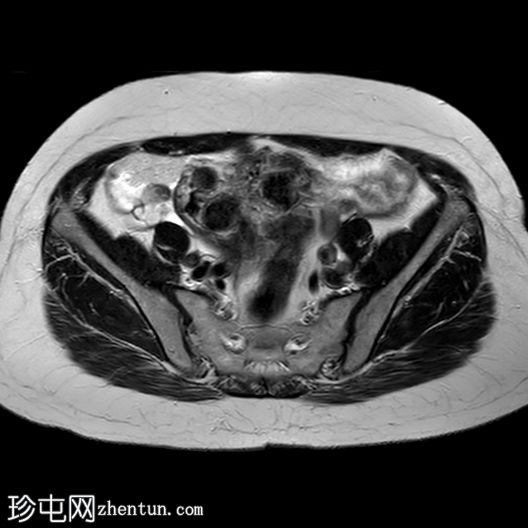

6个月前MRI检查

MRI

轴位

T2加权像

3.jpg

与既往CT同时进行的MRI检查显示子宫内有多发性T2低信号强度肌瘤,但在子宫右侧一个肌瘤内可见一处不均匀、中心高T2/囊性信号区。